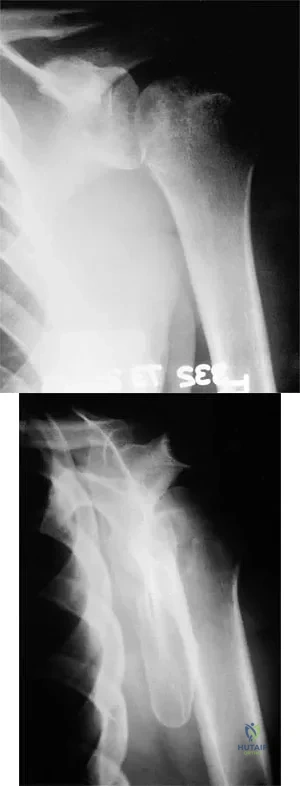

A 37-year-old electrician is diagnosed with a frozen shoulder after sustaining an electrical injury at work 2 weeks ago. Examination reveals that he cannot actively or passively externally rotate or abduct the arm. The glenohumeral joint and scapula move in a 1:1 ratio. Radiographs are shown in Figures 15a and 15b. The best course of action should be